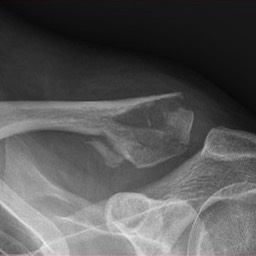

What do Distal Clavicle Fractures Look Like on X-ray and CT?

X-RAY

Diagnosis of a distal clavicle fracture is made with history, then a plain xray of the clavicle and in a lot of cases a CT scan. With new 3D CT scan imaging, separation of bony fragments can be well visualised which helps for possible surgical planning.